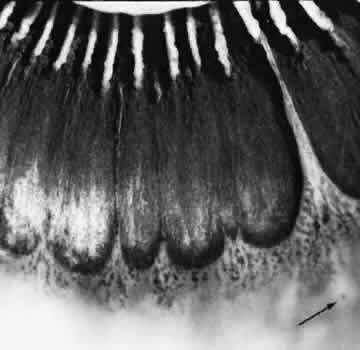

CYSTIC RETINAL TUFT

Larger than a noncystic tuft, the cystic retinal tuft is a nodular projection of retinal tissue that extends from a vitreous attachment at the apex to a base that is more than 0.1 mm in diameter and surrounded by cystic retinal degeneration (Fig. 38). Single ormultiple cystic retinal tufts may be located within or posterior to the vitreous base. On microscopic appraisal, the tuft, attached internally to a vitreous strand, is composed of degenerated and proliferated retinal cells that may contain a few pigment granules (Fig. 39). There may also be degeneration of the adjacent retinal pigment epithelium.

Fig. 38. Cystic retinal tuft in peripheral retina of a 14-year-old boy. Tuft measures 0.47 mm at its circular base, is 3.7 mm from the ora serrata, and contains many microcysts with dense walls. (× 19.)

Fig. 39. Microscopic features of the lesion seen in Figure 38. Surface of the tuft is irregular, with layer of dense-staining glial cells that partially surround subsurface microcysts. Degeneration of neurons, formation of microcysts, and pigment dispersion occur in deeper layers. Outer retina beneath lesion shows marked degeneration of photoreceptor cells. Patterns of vitreous over lesion are distorted, and coarse bundles of vitreous fibrils blend with irregular surface of tufts. (Periodic acid-Schiff; × 180.)

Cystic retinal tufts are present at birth; they are evident in 5% of adults, are bilateral in 6% of affected patients, and thus are detected in 2.5% of adult eyes (see Table 3). Although cystic retinal tufts show no quadrant predilection, 78% occur in the equatorial (extrabasal) zone, and 80% occur singly in eyes of affected patients.

On clinical examination, cystic retinal tufts are readily visualized and are distinguishable from noncystic tufts by size and other characteristics. Cystic retinal tufts are of importance because they may be avulsed by vitreous traction, with or without posterior vitreous detachment leading to retinal tear or retinal detachment.

Of patients with retinal detachment, an avulsed cystic retinal tuft is implicated in up to 7% of eyes. However, of all patients with a cystic retinal tuft, only 0.18% would develop retinal detachment due to this lesion. As such, prophylactic laser photo-coagulation for cystic retinal tuft is not recommended.35